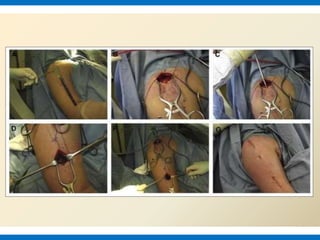

CASE 2

Proximally a 5-6cm longitudnal incision from the tip of acromion down the lateral aspect

of upper arm. The length and position of distal incision depends on the site of fracture and